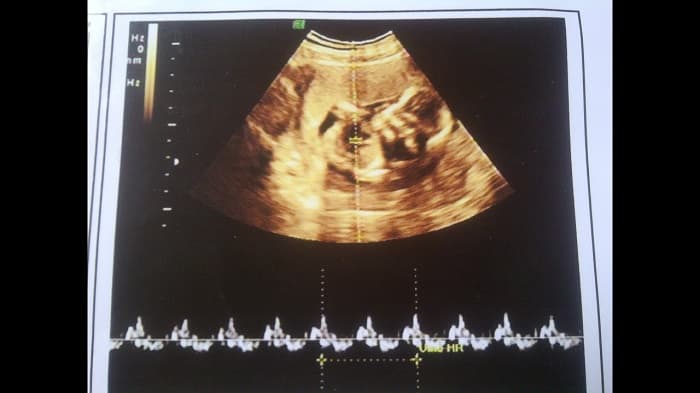

Nhịp tim thai 7 tuần là bao nhiêu?

Cho tới những tuần tiếp theo, tim thai sẽ tiếp tục phát triển về kích thước, khối lượng cho tới khi bé chào đời. Nhịp tim bình thường của thai nhi sẽ từ 120-160 nhịp/phút, tùy từng giai đoạn. Nếu thai nhi cựa quậy nhiều thì có lúc nhịp tim lên đến 180 nhịp/phút. Nếu tim thai đập dưới 110 nhịp/phút thì là tim thai yếu, bé sẽ gặp rất nhiều nguy cơ.

2. Tim thai ở tuần thứ 7

Tuần thứ 7 là một cột mốc quan trọng trong sự phát triển tim thai. Lúc này, trái tim đã được chia làm 2 buồng trái, phải. Ở tuần thứ 7, nhịp tim thai trung bình sẽ từ 90-100 nhịp/phút và tăng dần trong những tháng về sau. Bác sĩ có thể xác định được nhịp tim thai khi siêu âm qua đường âm đạo.

Tại thời điểm này, tim thai chỉ bé bằng một hạt gạo và mặc dù chưa hoàn thiện về cấu tạo nhưng trái tim đã thực hiện những chức năng nhất định. Nếu nhịp tim thai ở tuần thứ 7 dưới 70 nhịp/phút thì thai nhi sẽ đối diện với nhiều nguy cơ như chết lưu, dị tật, gặp những biến chứng nguy hiểm.